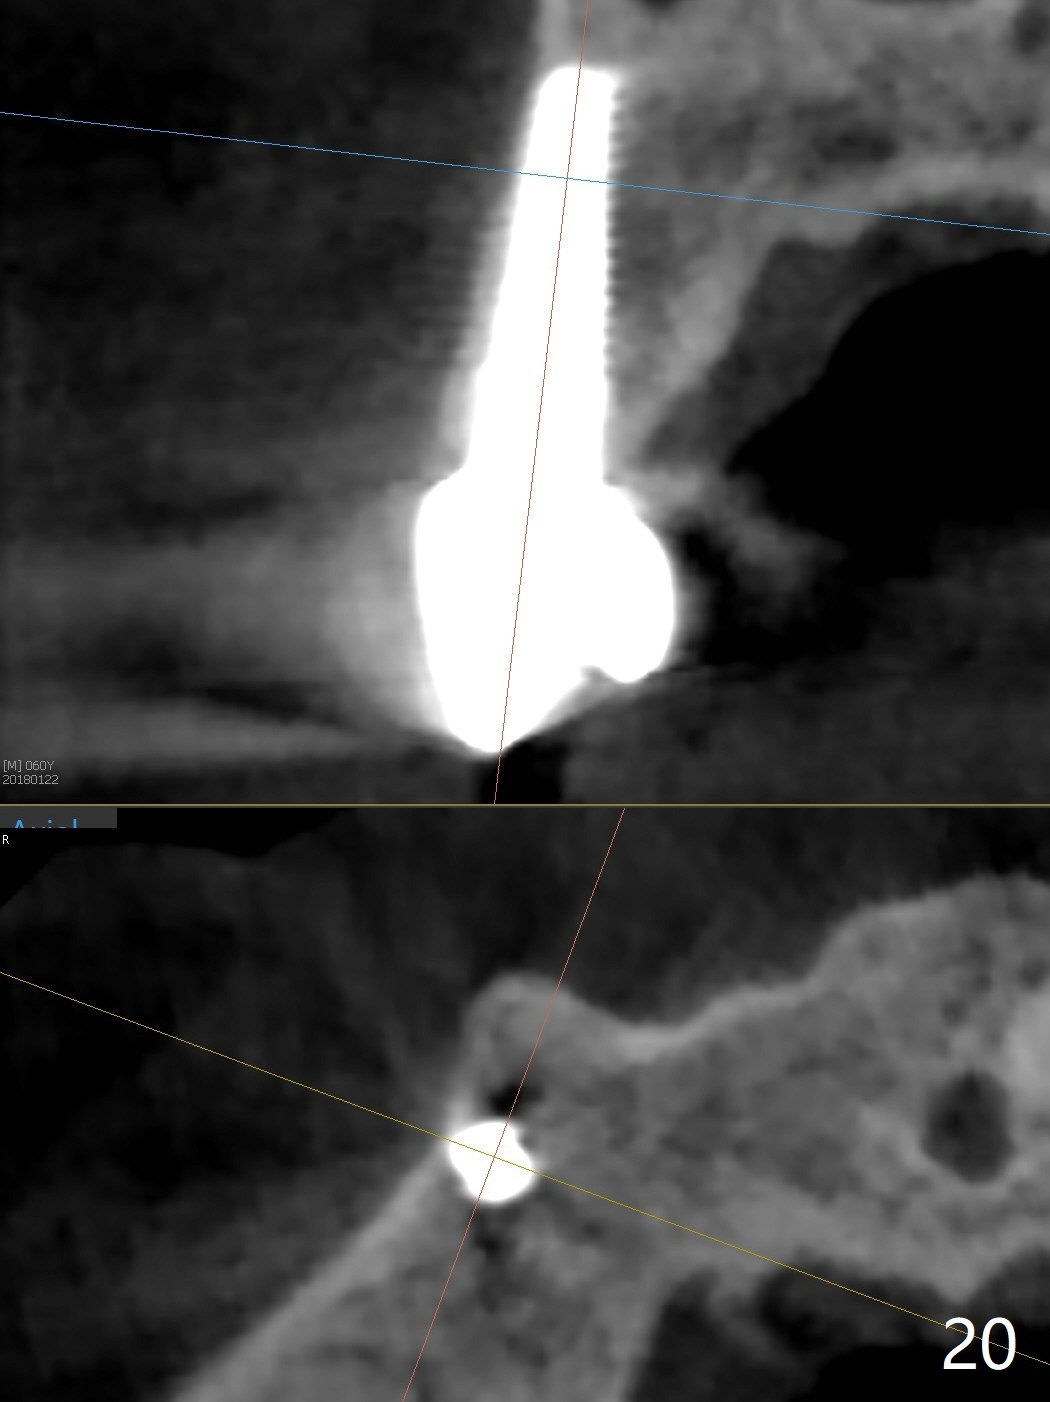

The long implant seems to be appropriate for the patient with periodontitis and bruxism (Fig.18, 2 years, 10 months post cementation). The implant appears to be placed buccally (B, Fig.19,20 (CBCT coronal and axial sections), 4 years, 5 months post cementation).